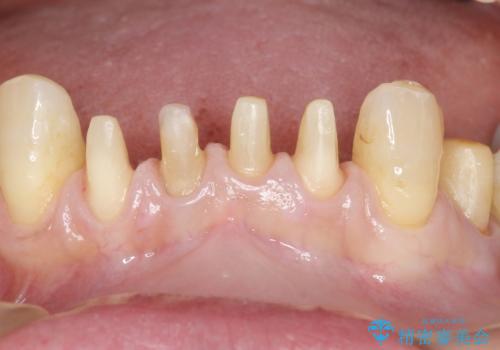

- 下の前歯が欠けてぐらぐらすることを主訴に来院された患者様です。

以前行った奥歯の治療により下顎前歯の動揺は改善傾向にあり顕著ではなかったのですが、欠けて黒くなっていることと少しの動揺が気になるとのことでした。

元気なうちに治療しておきたいという患者様の強いご希望により、下顎前歯の連結補綴と欠けている小臼歯の補綴治療を行いました。